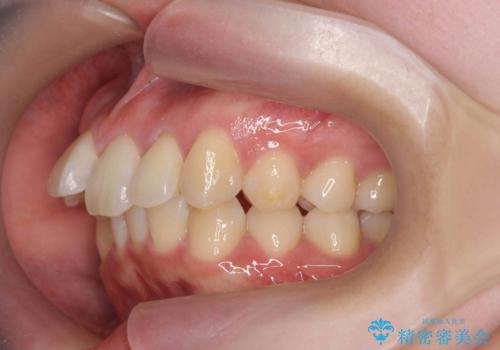

上の歯列を後ろに下げるのに、矯正用ミニスクリューを使用しています(インプラント矯正)

下の前歯を1本の抜歯にしていますので上下の正中は合わない仕上がりとなっております。その代わり奥歯のかみ合わせと抜歯の本数削減を優先しています。

また、上の前歯を下げるために抜歯という選択肢もありましたが、前歯の大きさを若干小さく削り、奥歯を後ろに下げるというのを試みて、難しいようなら抜歯という形で進めました。

結果、遠心移動もスムーズに進み大きく前歯を下げることができました。